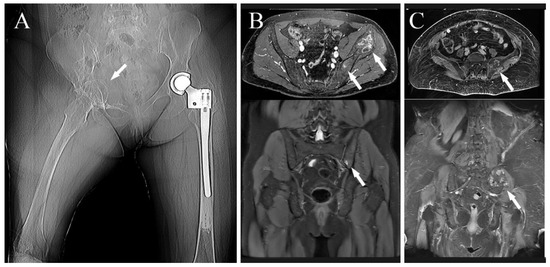

- The site: the aim of reconstruction after pelvic resection is to restore hip stability by giving the articulation a pivot. Acetabulum sparing is the keystone. Reconstruction can be performed with a hip prosthesis that includes a cup with an iliac stem when part of the anterior or posterior column is spared. When resection includes the acetabular roof (Figure 3A), an acetabulum with an iliac stem does not have sufficient bone support, so 3DPTCMP is a possible solution (Figure 3C right side); the 3DPTCMP should be linked to a spine stabilization to neutralize vertical cutting forces when resection includes the sacrum-iliac joint (Figure 5A,B).

- Prosthesis shape: most prostheses were constructed trying to reproduce normal bone anatomy (Figure 4A–C). Actually, this tactic could cause problems as wound dehiscence due to skin decubitus on the prosthesis; taking this into consideration, the option of designing a low-profile prosthesis has to be taken into account (Figure 5A,B): when the tumor involves the iliac wing, the prosthesis could simply connect the sacrum-iliac joint to the hip without reproducing the iliac wing’s shape (Figure 5A,B). Currently, several prosthesis designs are proposed in the literature.

- The pelvic ring restoration: several authors sustain the importance of restoring the connection between the sacrum-iliac area, the acetabulum and the symphysis [25,26]; other authors sustain a non-anatomical reconstruction [26,27]. Connection to the symphysis could be a more stable fixation at first (Figure 7B), but in the long term, this technique could increase the risk of osteolysis in the symphysis (Figure 7C) (case 3) and prosthesis loosening. Indeed, a connection with the symphysis can transfer the stress forces to the bone–prosthesis interface at the acetabular level every time that weight-bearing is on the contralateral side; contrariwise, when weight-bearing is on the side of the prosthesis, the stress forces are transmitted to the prosthesis–bone symphysis interface with hypothetical easier mobilization. Based on these concepts, connection to the symphysis has to be well evaluated; actually, a fascia lata allograft can be used to reconstruct the inguinal ligament and support the abdominal viscera when necessary (Figure 7C). The fascia lata also decreases the friction between the vessels and the prosthesis and therefore the risk of their damage, as happened in one case of our series, in which the patient died from iliac vein rupture (case 5). Instead, reconstruction of the ileo-pubic ramus has an important biomechanical value; indeed, it represents a fulcrum with the iliopsoas muscle, allowing it to act as a hip flexor; when the ileo-pubic ramus is not reconstructed, the iliopsoas collapses inside the pelvis, acting more as an adductor muscle, with a consequent loss of flexion activity. Based on these considerations, while symphysis fixation presents a rationale, ischium fixation is not recommended because it would transmit cutting forces to the bone–prosthesis interface every time the patient sits down.When the tumor also involves the Enneking and Dunham T1 and 4 areas, spine stabilization is suggested to neutralize the cutting forces that act on the prosthesis (Figure 4A,B); in these cases, a median incision is completed to perform a bilateral stabilization; bone fusion is suggested to decrease the risk of pedicle screw loosening. This surgical step can be performed during tumor removal surgery or in a second moment to decrease the impact of a massive surgery on the patient. Actually, spine stabilization could become unnecessary in the future if osteointegration improves. A possible solution to improve osteointegration could be the use of a composite prosthesis composed by a 3DPTCMP as a scaffold for a vascularized autologous bone graft as a fibular flap; in that case, the 3DPTCMP should assure primary stability, whereas the fibular flap should give osteointegration and stability without the need of spine stabilization. Recently, Lu et al. proposed a similar composite structure for diaphyseal reconstruction after bone tumor removal with good results; actually, that technique could also be suggested for reconstruction in the Enneking and Dunham T 1 and 4 areas when the acetabular roof is spared [28].